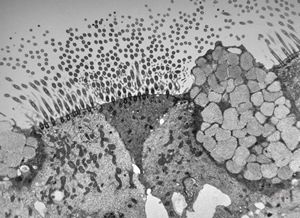

F,7y. | immotile cilia syndrome - nasal mucosa

M,8y. | immotile cilia syndrome - bronchus

F,5y. | immotile cilia syndrome - nasal mucosa

M,12y. | immotile cilia syndrome - nasal mucosa

F,49y. | normal kinocilium - bronchus

F,5y. | immotile cilia syndrome - trachea

F,5y. | immotile cilia syndrome - rootlet of kinocilia

M,18y. | immotile cilia syndrome - bronchus - microvillous prominence

M,18y. | immotile cilia syndrome - bronchus